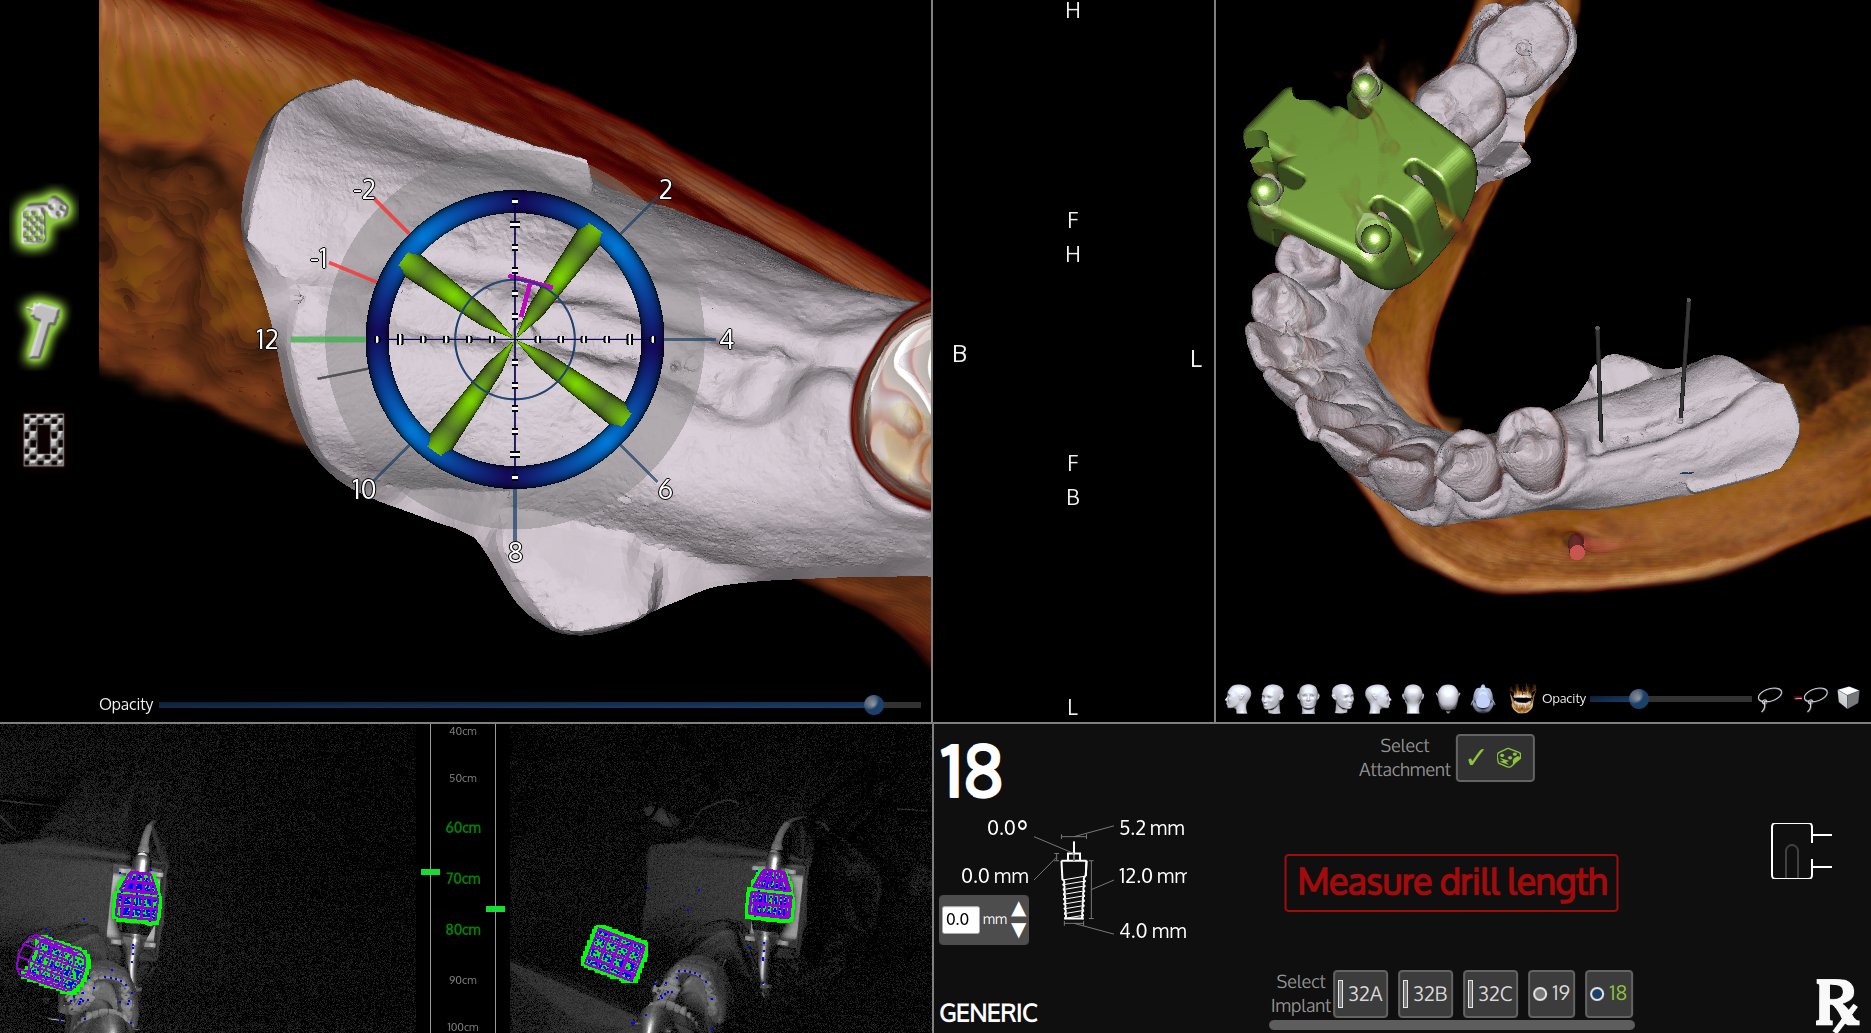

Calibration In Dynamic Navigation Surgery In Implamt

Browse our specialized Calibration In Dynamic Navigation Surgery In Implamt portfolio with numerous expertly curated photographs. optimized for both digital and print applications across multiple platforms. providing reliable visual resources for business and academic use. Each Calibration In Dynamic Navigation Surgery In Implamt image is carefully selected for superior visual impact and professional quality. Perfect for marketing materials, corporate presentations, advertising campaigns, and professional publications All Calibration In Dynamic Navigation Surgery In Implamt images are available in high resolution with professional-grade quality, optimized for both digital and print applications, and include comprehensive metadata for easy organization and usage. Our Calibration In Dynamic Navigation Surgery In Implamt collection provides reliable visual resources for business presentations and marketing materials. Whether for commercial projects or personal use, our Calibration In Dynamic Navigation Surgery In Implamt collection delivers consistent excellence. The Calibration In Dynamic Navigation Surgery In Implamt archive serves professionals, educators, and creatives across diverse industries. Regular updates keep the Calibration In Dynamic Navigation Surgery In Implamt collection current with contemporary trends and styles. Advanced search capabilities make finding the perfect Calibration In Dynamic Navigation Surgery In Implamt image effortless and efficient. Multiple resolution options ensure optimal performance across different platforms and applications.